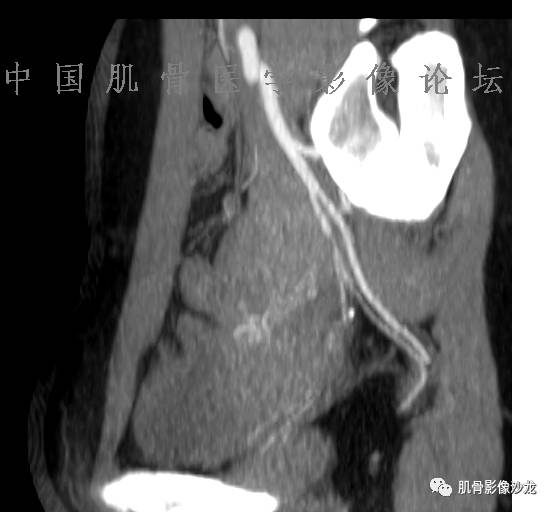

患者2月前无明显诱因下感右腿疼痛、麻木,疼痛呈持续性,发作时无法行走,休息后可缓解。当时无明显肿块,患者遂至当地医院就诊,查X片见右髂骨骨质破坏。6周前患者自觉右髋部渐大肿块,初肿块较小,后肿块逐渐增大,现肿块约12*10cm大小,有压痛。患者遂至我院就诊,查MRI:右髂骨异常信号,伴软组织肿块。ECT、肺CT未见转移。现患者为求进一步治疗,门诊拟“右髂骨肿块 ”收治入院。 患者发病来,神清,精神可,胃纳夜眠可,二便无殊,体重无明显变化。

1、软骨肉瘤可以有膨胀性骨质破坏(病例3,4),可以有溶骨性骨质破坏(病例2),局部皮质因为破坏变薄,中断 ;

2、软骨基质T2WI高信号,软骨小叶分叶状,也就会出现高老师提到的骨内膜扇贝形压迹。一般认为骨内膜扇贝形压迹超过骨皮质厚度的2/3是软骨肉瘤在长管状骨的特征性表现。如上图。3、软组织肿块或肿胀;

4、 钙化,环形,弓形,边缘模糊 ;

5、增强后进行性延迟,不均匀分割状强化, 会强化的纤维间隔,软骨小叶不会强化,关于老师们说到的钙化,软骨肉瘤不一定会有钙化 。